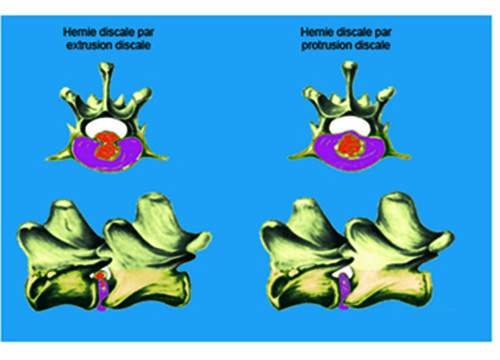

Le disque intervertébral peut dégénérer de deux façons :

Chez les races dites chondrodystrophiques : Teckel, Pékinois, Cocker, Bouledogue Français, et Beagle entre autres, le noyau pulpeux se transforme en un magma chondroïde plus ou moins calcifié. A la suite d'un mouvement un peu violent ou de mouvements répétés, le disque calcifié passe au travers de l'anneau fibreux dorsal et vient se déverser brutalement dans le canal médullaire en comprimant la moelle épinière : il s'agit d'une hernie discale par extrusion discale. La survenue de la hernie est aigüe et le traumatisme médullaire souvent important du fait de la vitesse d'extrusion du disque. Ce type de hernie discale est dit Hansen I.

Chez les races non chondrodystrophiques : la dégénérescence discale se fait sur un mode fibreux, à la faveur d'une fragilisation de l'anneau discal dorsal, le noyau pulpeux dégénéré fait petit à petit protrusion dans le canal vertébral et vient progressivement comprimer la moelle épinière en entrainant une démyélinisation progressive et une axonopathie irréversible. Cependant, l'évolution de la hernie peut aussi se faire de façon aigüe avec une protrusion plus rapide à la faveur d'un mouvement un peu violent, entrainant une dégradation rapide du statut neurologique avec paralysie brutale. Ce type de hernie appelée Hansen II est plutôt l'apanage des chiens de grand format.